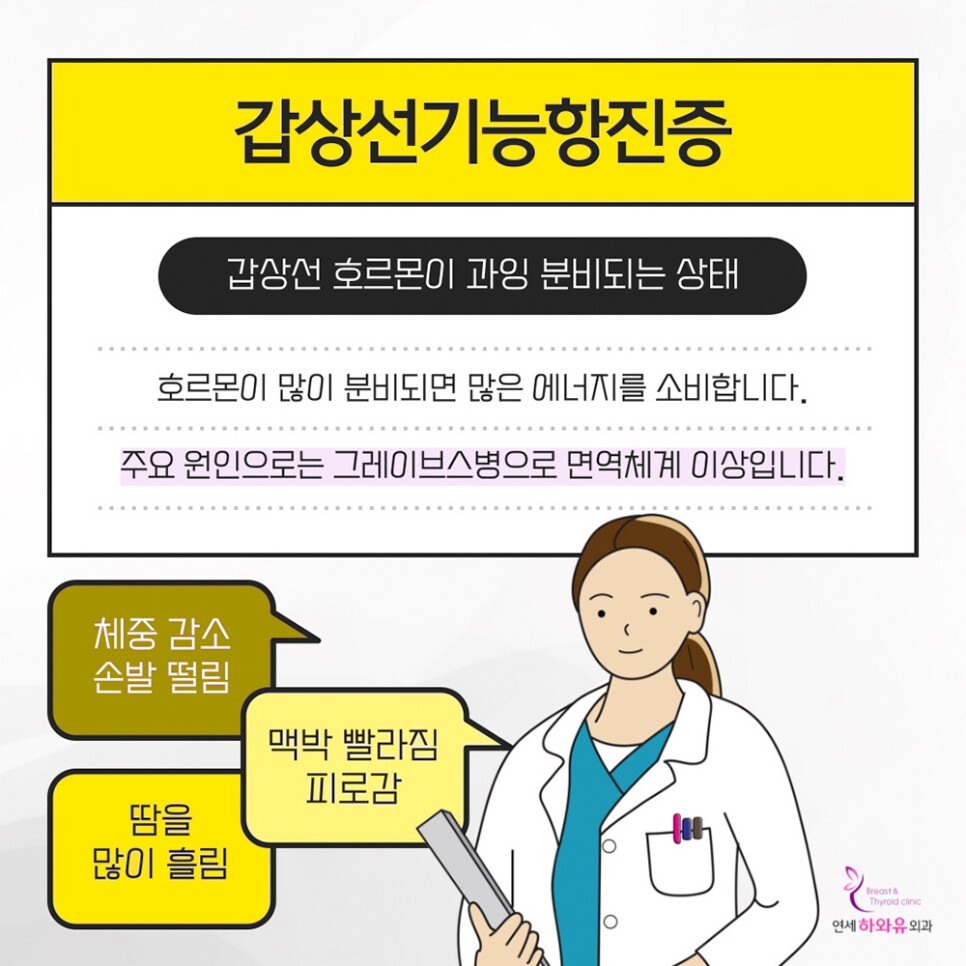

갑상선항진증이란?

갑상선에서는 체온 조절과 신진대사 등에 관여하는 호르몬을 분비하는데요, 어떠한 이유로 과도하게 분비되어 인체 대사가 증진되며 에너지 소모가 일어나게 되는 것을 갑상선 기능 항진증이라 합니다.

원인은?

갑상선항진증의 주된 원인은 자가면역질환인 그레이브스병입니다. 이 외에도 갑상선 호르몬제를 과다 복용한 경우 혹은 갑상선종이나 뇌하수체 선종이 있는 경우 종양에 의해 갑상선 자극 호르몬이 과도하게 분비되어 나타날 수 있습니다.

갑상선항진증 의심 증상

■ 더위를 많이 타고 땀이 유난히 많이 난다

■ 식욕은 늘거나 그대로인데 체중이 감소한다

■ 신경이 예민해지고 집중력이 저하된다

■ 손발이 떨리고 잠을 이루기가 어렵다

■ 맥박이 빨라지고 가슴이 두근거린다

■ 대변을 보는 횟수가 잦거나 설사를 한다

■ 무기력한 기분이 든다

■ 머리카락이 푸석하고 많이 빠진다

■ 생리가 불규칙해지거나 멈췄다

■ 눈에 이물감이 들고 튀어나온다

갑상선 기능 항진증이 발병하면 앞서 말한 듯이 초기에는 별다른 증상이 없거나 일상생활에서 흔히 겪을 수 있는 증상들로 나타납니다.

특징적인 것으로는 이유 없이 체중이 감소하거나 감정 변화가 심해지고 가슴이 두근거리는 현상, 손발 떨림, 목 앞 부근이 부어오르는 듯한 현상이 나타납니다.